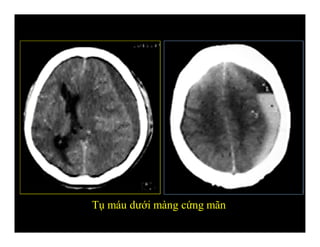

-Đứt các tĩnh mạch cầu nối

-Hình liềm

-Chạy qua các khớp sọ

-Không vượt qua các nếp màng cứng (liềm, lều

não)

-Tuỳ tụ máu cấp, bán cấp hay mãn mà đậm độ

khác nhau

TỤ MÁU DƯỚI MÀNG CỨNG

(Subdural hematoma)

Tụ máu dưới màng cứng mãn

Phân biệt tụ máu ngoài màng cứng và dưới màng cứng

-Đứt các tĩnhmạch cầu nối -Hình liềm -Chạy qua các khớp sọ -Không vượt qua các nếp màng cứng (liềm, lều não) -Tuỳ tụ máu cấp, bán cấp hay mãn mà đậm độ khác nhau TỤ MÁU DƯỚI MÀNG CỨNG (Subdural hematoma)

Tụ máu dướimàng cứng

Tụ máu dướimàng cứng mãn

Phân biệt tụmáu ngoài màng cứng và dưới màng cứng